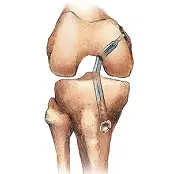

Knee Orthopedic Surgery